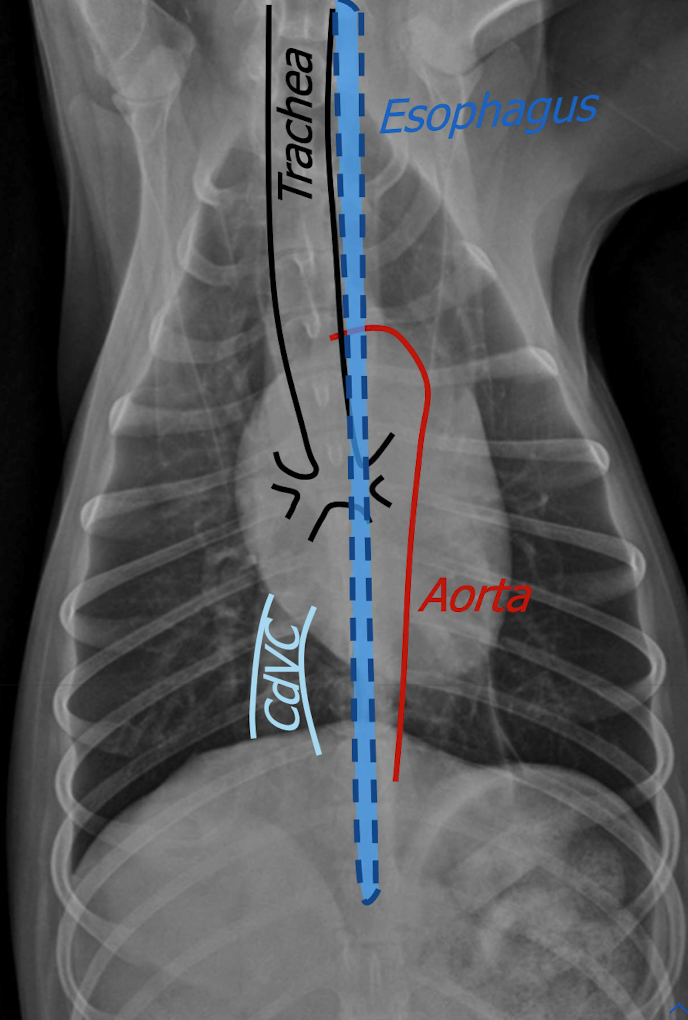

what is found in the area of the mediastinum

Heart

Aorta

Vena cava (Cd & Cr)

Trachea

Esophagus

Thymus

Lymph nodes

what is found in the craniodorsal mediastinum

Great vessels

 Trachea

 Esophagus

 Cranial mediastinal lymph nodes